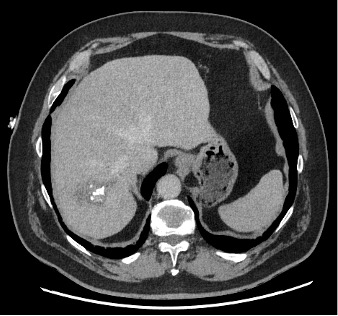

Ce CT-scanner, initialement réalisé chez une patiente de 70 ans à la recherche d’une dissection aortique scanner, met fortuitement en évidence une lésion hépatique.

Les douleurs de la patiente ont bien évolué sous traitement symptomatique. Son bilan sanguin avec FSS, CRP, tests hépatiques et pancréatique est dans la norme. Au vu de la présence de lésions kystiques hépatiques présentant des calcifications et des zones de nécrose sur le scanner, une sérologie pour l’échinococcose alvéolaire (EA) est demandée.